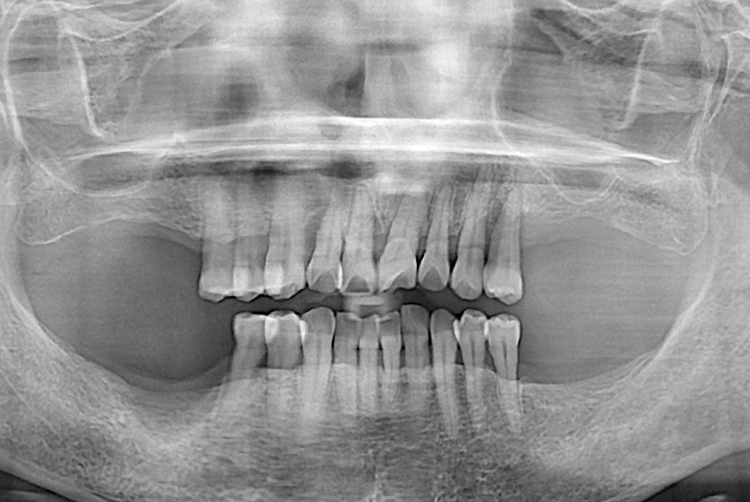

치료전 : 2018-06-21

세종치과는 많은 환자와 다양한 케이스를 바탕으로 항상 편안한 임플란트 수술을 제공하고자 노력하고,

오래동안 튼튼히 쓸 수 있는 임플란트 수술을 가장 큰 목표로 삼고 있습니다